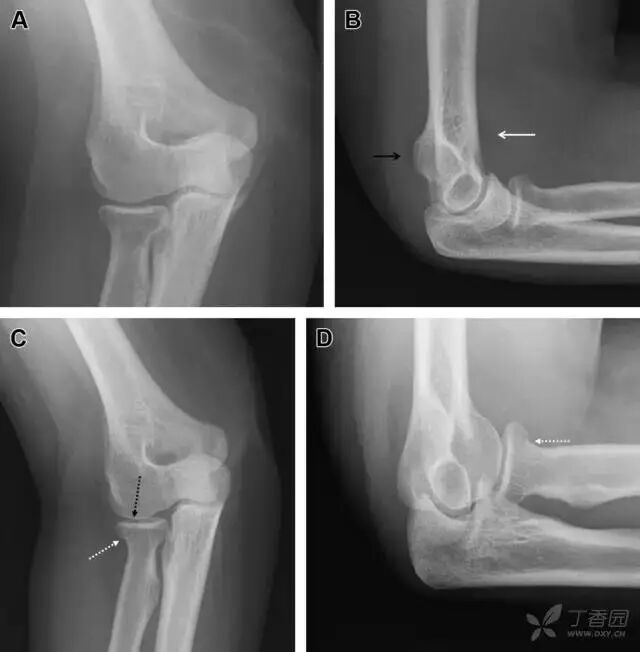

24无移位的桡骨头/颈骨折

多发生于摔倒时,手掌撑地,受到轴向、外翻应力所致。常规的前后位片容易漏诊,常需加拍内斜位、外斜位、桡骨头-肱骨小头位片。后脂肪垫可见(位于鹰嘴窝内,一般不可见)和/或前脂肪垫抬高常提示骨性损伤。

图 2 桡骨头骨折。前后位(A)和侧位(B)片示后脂肪垫抬高(黑色箭头),前脂肪垫抬高(白色箭头),呈「帆船征」,其它表现正常;外斜位(C)和桡骨头–肱骨小头位(D)示桡骨头关节内骨折线(虚线黑箭头)累及桡骨颈(虚线白箭头)